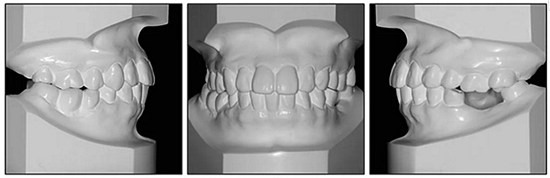

36歲;女性;尋求下頜左后方區(qū)域間隙管理的建議(圖1和圖2),通過(guò)治療獲得了良好的牙頜面效果(圖3和圖4)。她被診斷患有骨性I類(lèi)和代償性牙性II類(lèi)錯(cuò)合畸形,并且上頜左側(cè)尖牙缺失(圖1和2)。大約七年前,由于不可修復(fù)的齲齒,拔除了下頜左側(cè)第一和第二磨牙(圖5)。37相鄰的第三磨牙向近中移動(dòng)并傾斜入間隙,導(dǎo)致無(wú)牙頜間隙減小至約14 mm(圖2和圖5)。臨床和影像學(xué)評(píng)估顯示多發(fā)性齲損和在下頜右側(cè)567處有一不良的固定橋修復(fù)體(圖1和5)。此外,下頜左中切牙缺失,造成下頜中線(xiàn)向左側(cè)偏移約3 mm(圖1和圖2)?;颊咦栽V,她的右上第一前磨牙和左上尖牙在13歲時(shí)由其家庭牙醫(yī)拔除,因?yàn)樗鼈儽蛔枞筋a側(cè)萌出(圖1)。上頜第二磨牙缺失(未知病因),并且相鄰的第三磨牙已經(jīng)轉(zhuǎn)移到第二磨牙間隙中。如補(bǔ)充材料所示,美國(guó)正畸學(xué)差異指數(shù)DI是28分。種植體部位(下頜左側(cè)和右側(cè)第一磨牙)由于復(fù)雜性得到額外4分(補(bǔ)充材料)。

圖2. 治療前牙齒模型